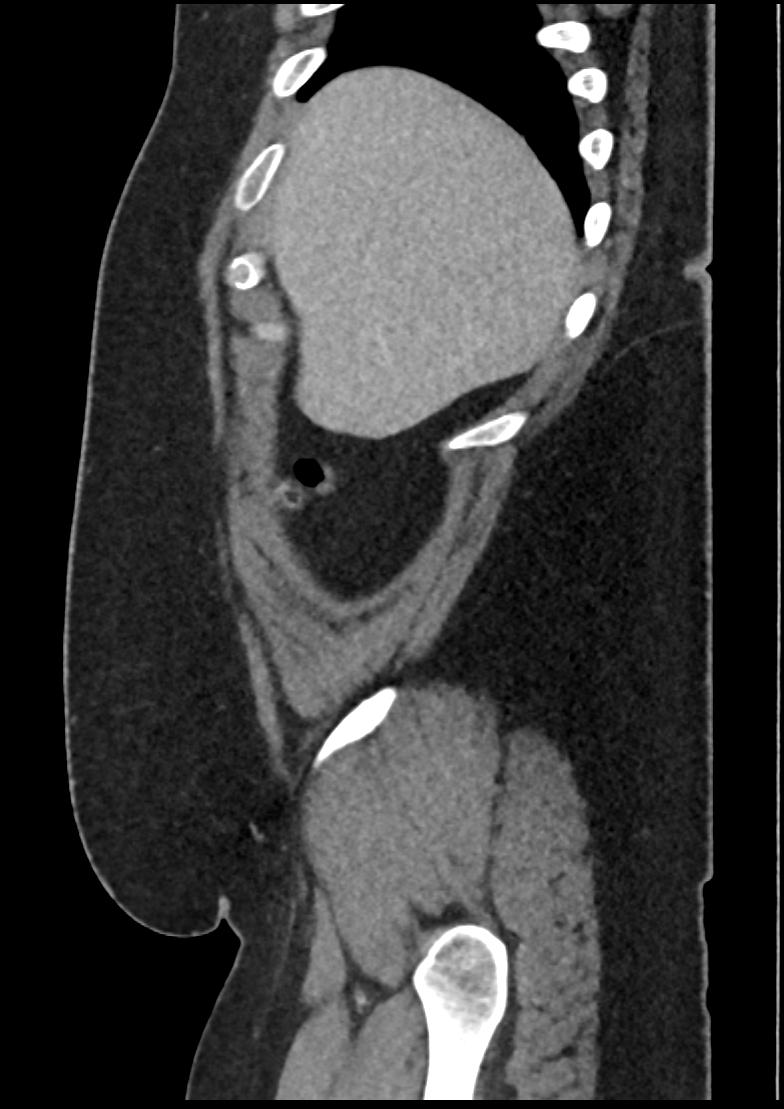

Patient: Padmakumar A. , *1988-04-24, PID: 3000069741773230809

Study Description: CT ABDOMEN

Image Series: Abdomen Sag 3mm [4]

<< Previous | Image 36 of 158 | Next >>